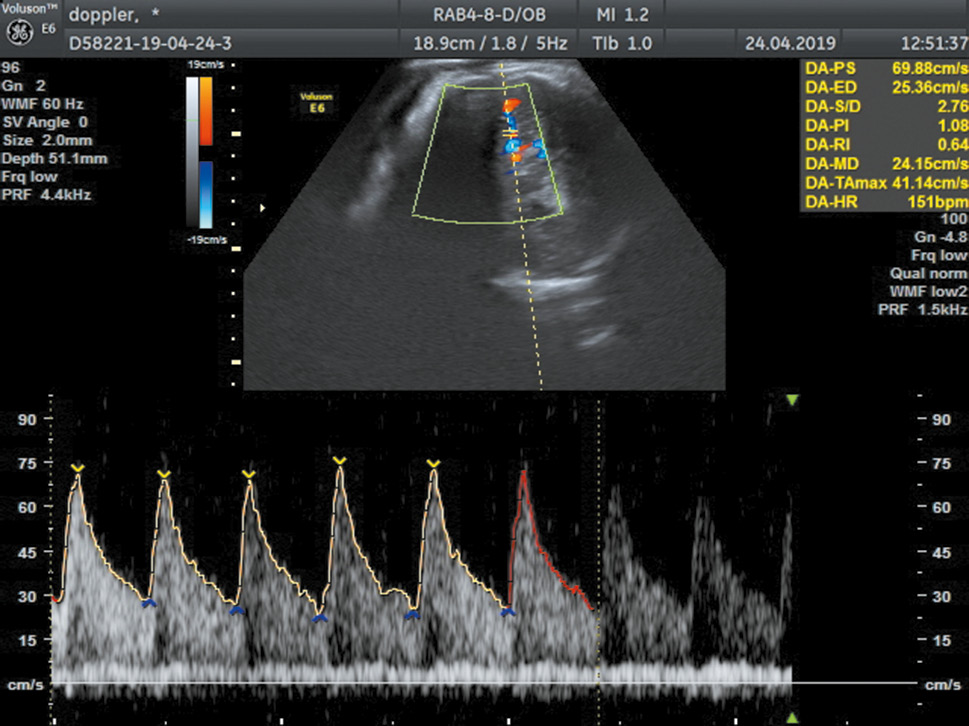

Ультразвуковое и доплерометрическое исследование всем беременным проводили с помощью аппаратов Volusson E6, Volusson S6, Medison Accuvix V20 и трансабдоминальных конвексных датчиков 3,5–5 МГц.

Доплерометрию в сосудах пуповины выполняли в свободной петле, то есть на удалении от места прикрепления пуповины к плаценте и впадения в тело плода. Кровоток в СМА исследовали при увеличении изображения головки плода, с помощью цветной доплерометрии выводили СМА, калиперы спектрального доплера располагали чуть выше отхождения сосуда от виллизиева круга. Индекс резистентности в вышеназванных сосудах измеряли несколько раз (3–5 раз), при этом учитывали наименьшие индексы для артерии пуповины и наибольшие для СМА.

Частотный фильтр устанавливали на уровне 60 Гц, угол инсоляции не превышал 30°, контрольный объем подбирали таким образом, чтобы он перекрывал диаметр сосуда (рис. 1). Регистрацию и оценку профиля кровотока выполняли в условиях двигательного покоя и апноэ у плода, при ритмичной и нормальной частоте его сердечных сокращений, соответствующей гестационному сроку. Предпочтение отдавали автоматической оценке скоростей кровотока. Использовали стандартные индексы резистентности, за ЦПО взято отношение пульсационного индекса (ПИ) в СМА к ПИ в артерии пуповины.

Рис. 1. Пример измерения скоростей кровотока в средней мозговой артерии

Fig. 1. Example of measuring Doppler indices in the middle cerebral artery